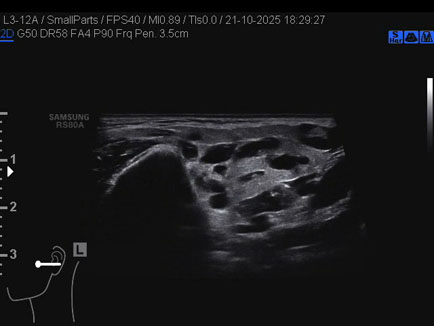

Ecografia del: 21/10/2025

Strumento: Samsung

Sonda: Lineare

Età Paziente: 50 anni

Commento all'esame: 50enne con stenosi del dotto di Stenone sn ed ectasia del dotto medesimo a dx.

Conclusioni: stenosi del dotto di Stenone sinistro (left Stensen's duct stenosis).